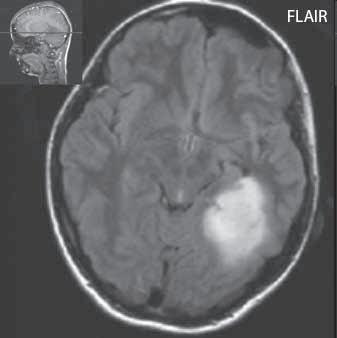

I 2 1 Difuzní astroc ytom low grade

I 2 2

I 2 3

I 2 4

astrocytom